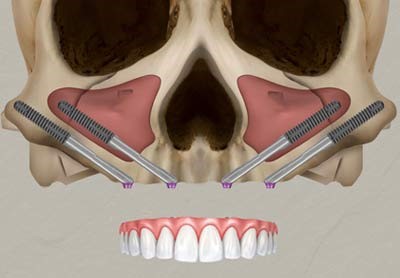

Zygoma Implant – kỹ thuật cấy ghép implant vào xương gò má (zygomatic bone), được phát triển bởi Giáo sư – Tiến sĩ Per-Ingvar Brånemark, chính là giải pháp đột phá cho những trường hợp này.

Zygoma Implant là loại implant dài hơn implant thông thường (30 – 55 mm), được đặt vào vùng thân xương gò má – vùng xương cứng, dày và ít tiêu theo thời gian.

3. Phẫu thuật cấy ghép

- Implant được đặt chính xác theo kế hoạch kỹ thuật số